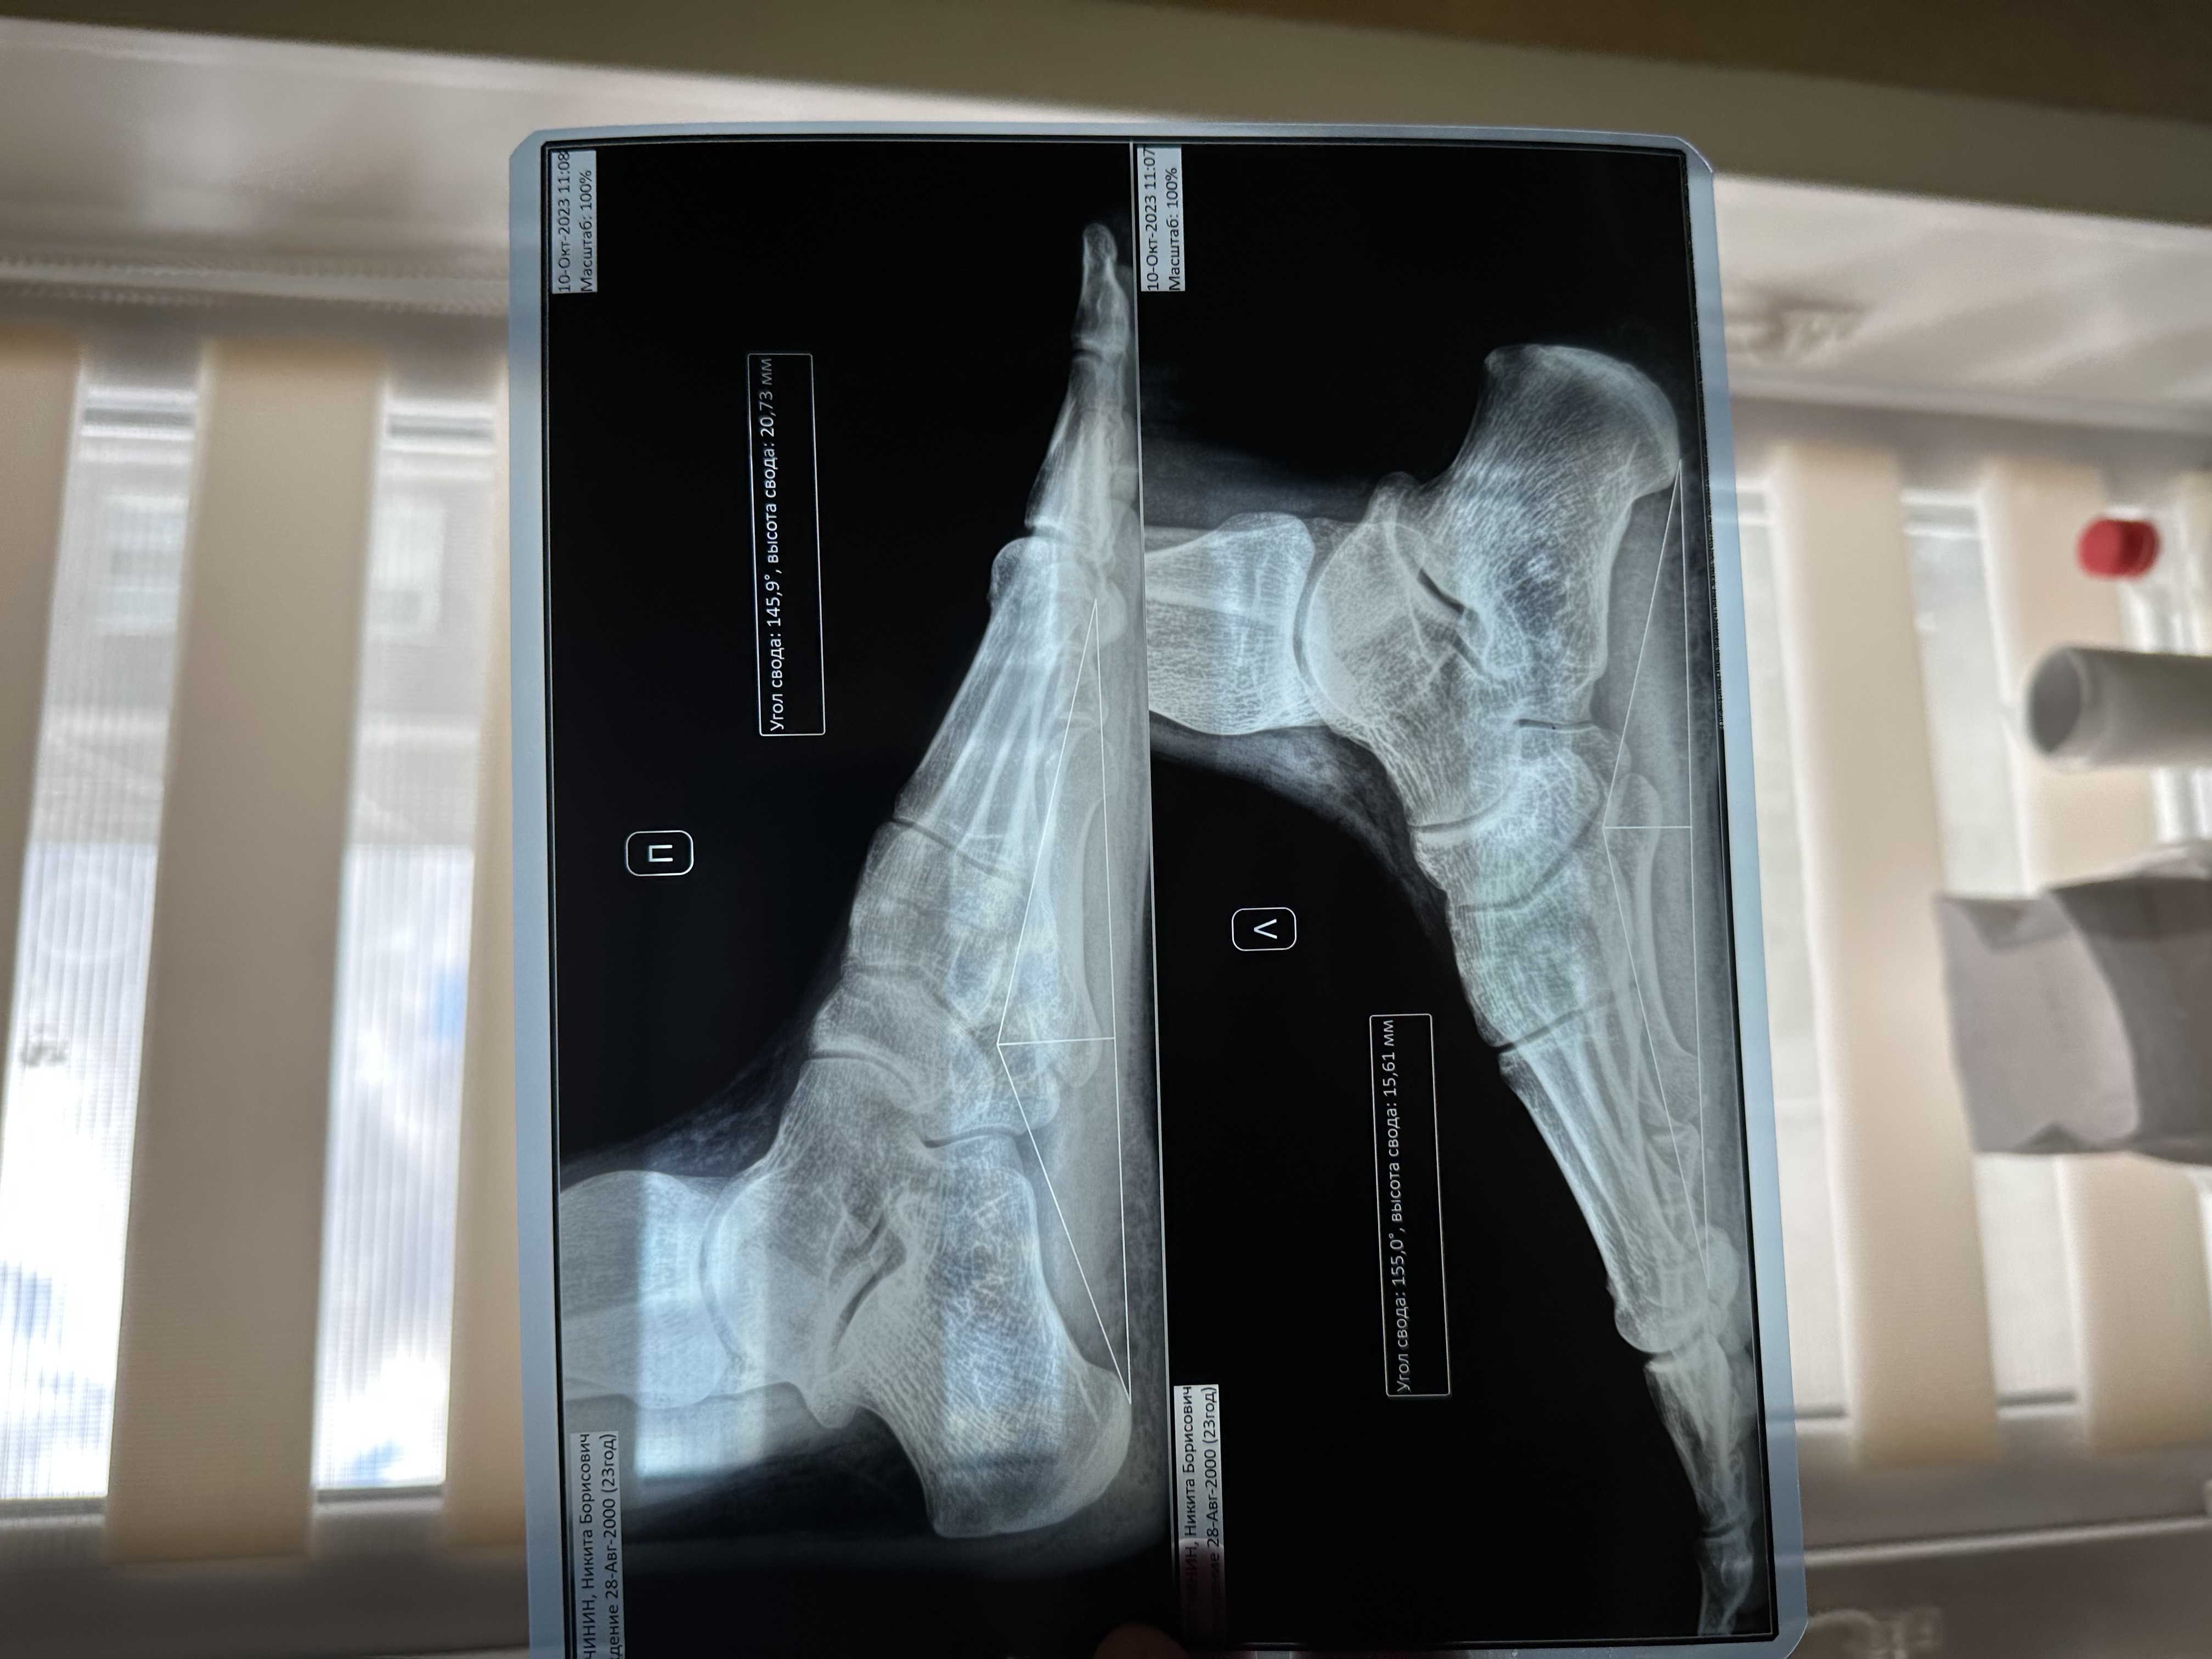

Снова здравствуйте. Прошел ортопеда-травматолога в областной поликлиннике. Направил на ренгтен стоп и повторную энмг, поставил плоскостопие, артроз таранно-ладьевидного сустава и невропатию большеберцового нерва - все под вопросом. Ренгтен показал 2 и 3 степень плоскостопия, энмг показало абсолютно здоровый нерв, врач сказала что предыдущий результат сильно занижен.

Завтра с утра иду делать игольчатую энмг в другую больницу, на всякий случай, после этого на повторный прием. Как будут результаты отпишусь сюда. Прикладываю то, что сегодня получил. На ренгтене есть какие-то признаки артроза?

Сделал игольчатую энмг и сходил на повторный прием к ортопеду-травматологу. На данный момент выставили плоскостопие 2 и 3 степени и артроз 1 степени. При этом градус по снимку 155, но ренгтен делался утром на отдохнувшей стопе. Ортопед обьяснил что 3 степень как ни крути уже есть.

Угол продольного внутреннего свода ровно 155 градусов - это 2 степень продольного плоскостопия.

В связи с чем я не удивлюсь, если врач-хирург районного военкомата по такому медицинскому заключению врача-травматолога-ортопеда и результатам рентгенографии не будет направлять вас на дополнительное обследование, а сразу на месте присвоит призывную категорию годности "Б-3" по статье 68, пункту "г" Расписания болезней. Но может и направит - смотря как вам повезёт.

Так же сходил сделал повторный ренгтен стоп в платной больнице - результат удивил. Результат почти такой же как ровно 9 месяцев назад, на ренгтене не было никакой опоры чтобы стоять ровно, да и вообще вся процедура выглядела очень странно. Там же сделал копию результата от января месяца. И выходит так что плоскостопие прыгало от 144 градусов до 155, а потом обратно до 144.

Приложил результаты в порядке получения. 1 и 3 делал в платной больнице, 2 в областной по направлению ортопеда.

Скажите, можеть быть такая погрешность? Попробовать сделать в каком-нибудь ортопедическом центре?

Нет, не может.

Для военкомата рентгенография стоп должна выполняться в боковой проекции в положении стоя с полной статической нагрузкой на исследуемую стопу - это значит, что в момент проведения исследования вы должны стоять на одной ноге, а вторую держать на весу.

Учитывая вышесказанное, естественно, вам имеет смысл выполнить ещё одну - контрольную рентгенографию стоп в боковой проекции в положении стоя с полной статической нагрузкой на исследуемую стопу, желательно в государственной больнице высокого ранга (например, в областной больнице) через раздел платных услуг, после чего обратиться к врачу-травматологу-ортопеду в этой же больнице для постановки диагноза.